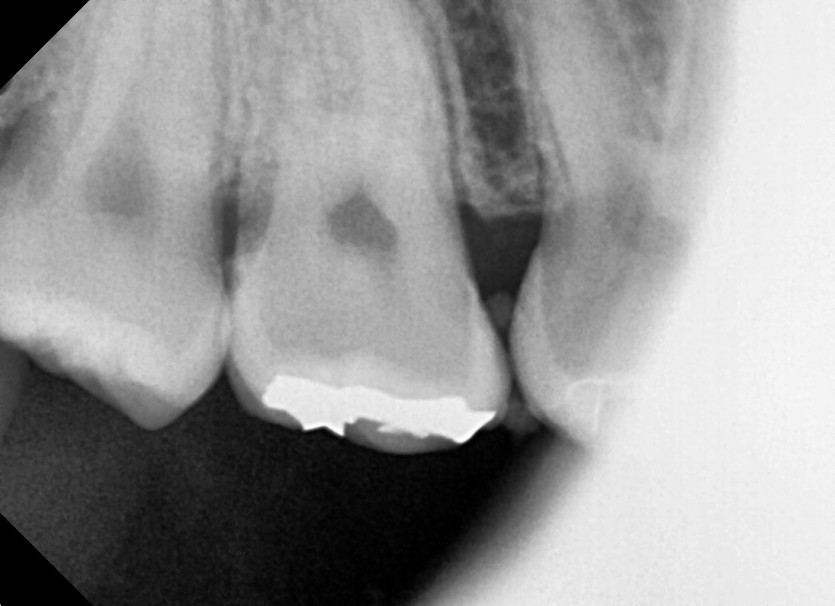

#18,48 사랑니 발치

구강 외과 전문의가 당일 발치했습니다.